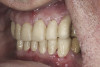

(23.) Provisionals, right lateral, closed view.

Figure 23

(24.) Provisionals, anterior, closed view.

Figure 24

(25.) Provisionals, left lateral, closed view.

Figure 25